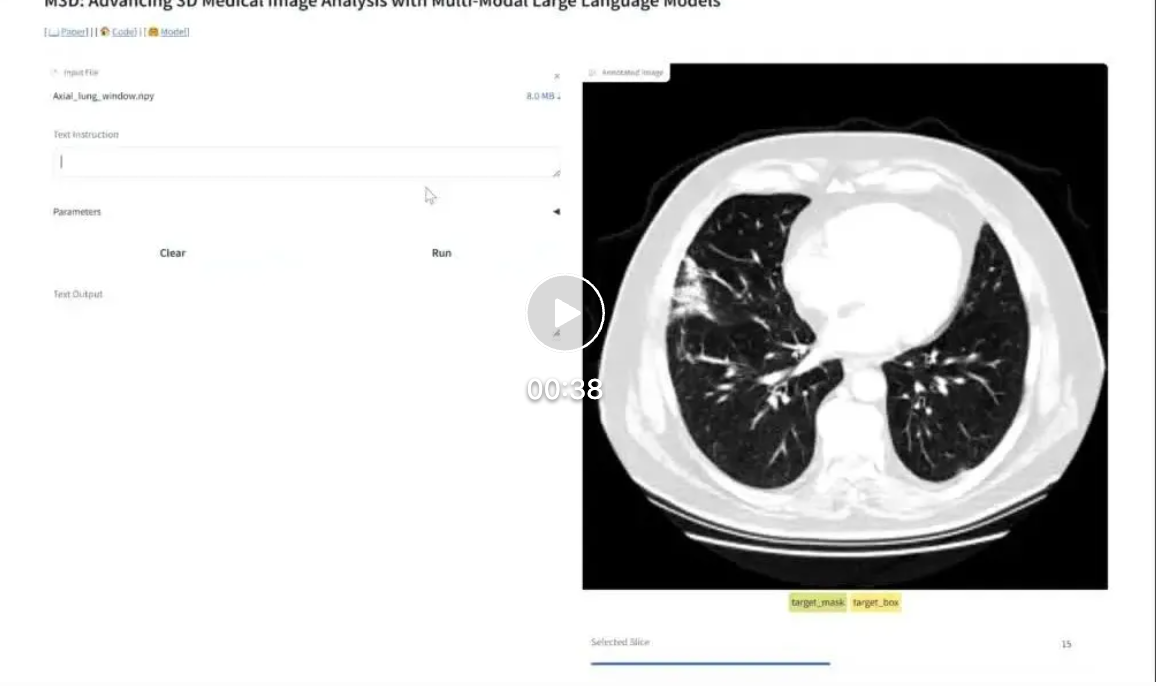

线上Demo视频。

近期,我们提供了更小和更强的 M3D-LaMed-Phi-3-4B 模型,并增加了线上 demo 供大家体验!